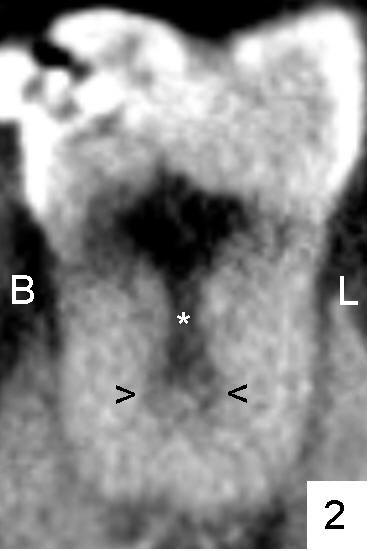

一两个月前三十三岁女士右下七号牙(#31)近中深龋做树脂修复,近来冷热痛,下周五她回诊所诊治。她牙齿问题较多,尤其是左上六缺失太久,植牙困难,所以拍摄CT。右下七号牙根管治疗前,研究CT根管解剖。图一,四,七是CT合成图像:右上角是三维图片(3D),右下显示七号牙矢状切面(S: sagittal),左上横断面(A: axial),左下冠状面(C: coronal),在每张CT合成图像中,粉红色,绿色以及蓝线代表其它断面切断平面。图一(左上角)中,M表示近中根, D远中根。图一,四,七分别代表近中根上,中,下三分之一断面分析。重点讨论冠状面(图二,五,八)。

近中根上三分之一好像是单根(图二*以及图一左上),快到中三分之一根管一分为二(图二箭头:B颊侧,L舌侧;图四左上箭头),中三分之一近中舌侧根管仿佛有两个侧枝根管(图五箭头),尽管下三分之一根管又融合(图八*,图七左上横断面:单个扁根管),中三分之一近中两个根管必须分别清洗(图六红色粉红色:两个扩大针),之前应该扩大根管进口(图三A: access,与图二对比)。如果偷懒或者事先无知而遗留一个根管,往后处理并发症可麻烦。本例病人马上要到老美牙学院上学了。